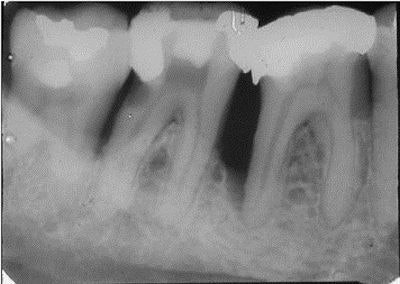

The patient presented to his dentist with deep periodontal pockets and bone loss on the distal roots of his lower right first and second molars (Nos. 30 and 31).

Root canal therapy was done on the mesial roots of both molars, and the mesial canals were obturated with Pulpdent Root Canal Sealer (Pulpdent) using the Pressure Syringe technique. The teeth were hemisected and the distal roots were removed.

This enabled us to use the natural roots of his teeth for abutments instead of placing implants, thus sparing the patient from the surgery.

A temporary was made until healing occurred. Then a fixed bridge was crafted. The radiograph below was taken seven years later and shows healthy bone and the bridge in place.